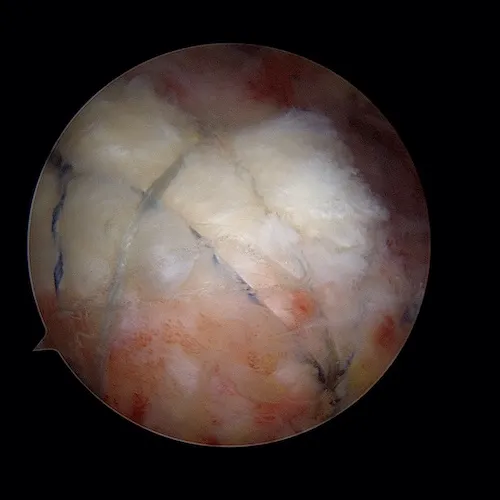

La rupture tendineuse est visualisée dans l'espace bursal sous la forme d'un "trou" dans le tendon. Les fibres tendineuses parthologiques sont réséquées afin de ne garder que du tendon sain. C'est ce tendon qui va être ensuite réinséré sur l'os.

La surface osseuse est ensuite préparée. L'os est avivé grâce à une fraise motorisée. Ce geste permet la revascularisation du tendon réinséré et la cicatrisation sur l'os.